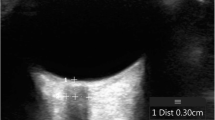

Subjects were placed in the supine position and images were obtained through a closed eyelid. A 13–6 MHz linear array ultrasound transducer (L25x transducer with a Sonosite M-Turbo Ultrasound Machine, SonoSite Inc, Bothell, WA) was used with the ophthalmic preset thus minimizing the power and acoustic output of the ultrasound system. The probe was placed gently on the upper eyelid. The ONSD was measured in a direction perpendicular to the axis of the nerve, in each eye, in the horizontal and sagittal plane, 3 mm behind the optic nerve head (Fig. 1), for a total of four measurements per subject.